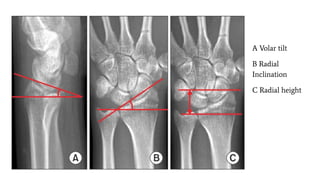

Radial Height & Inclination

Radial height is assessed on the PA view. It is a measurement between 2 parallel lines that are

perpendicular to the long axis of the radius. One line is drawn on the articular surface of the

radius, and the other is drawn at the tip of the radial styloid. The normal radial height is

9.9-17.3 mm.Measurements of less than 9 mm in adults suggest the presence of comminuted or

impacted fractures of the distal radius.

Radial inclination is measured on the PA view; this is a measurement of the radial angle. A line

is drawn along the articular surface of the radius perpendicular to the long axis of the radius,

and a tangent is drawn from the radial styloid. The normal angle is 15-25º.Abnormal

inclination of the distal radius may be a reflection of an impaction fracture of the distal radius

Volar/Palmar tilt

The volar tilt, or volar inclination, is measured on the lateral view. A line perpendicular to the long axis of the

radius is drawn, and a tangent line is drawn along the slope of the dorsal-to-volar surface of the radius. The

normal angle is 10-25º. A negative volar tilt indicates dorsal angulation of the distal, radial articular surface

A Volar tilt

B Radial

Inclination

C Radial height